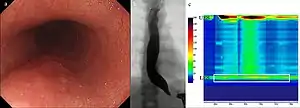

Para el diagnóstico se utilizan técnicas diversas de imágenes como: la Esofagoscopía, la radiología y la manometría.

Manometría esofágica

El diagnóstico es confirmado por medio de una Manometría esofágica de alta resolución, que mide las presiones del esófago mediante una sonda nasoesofágica y permite comparar las presiones en situación basal y durante la deglución.[8] Se inserta un tubo delgado a través de la nariz, y se le instruye al paciente a deglutir varias veces. La sonda mide las contracciones musculares en diferentes partes del esófago durante el acto de la deglución. La manometría revela la falla del EEI para relajarse con cada deglución y la falta de peristaltismo funcional del músculo liso en el esófago.

Endoscopia

Para descartar «complicaciones» se suele acudir a una endoscopia digestiva alta.

Permite confirmar el carácter funcional del afinamiento terminal del esófago, al vencerlo mediante una suave presión del endoscopio. Esto no ocurre cuando la estrechez es orgánica, por inflamación o neoplasia.

La endoscopía es necesaria para descartar otras patologías, antes de cualquier tratamiento.